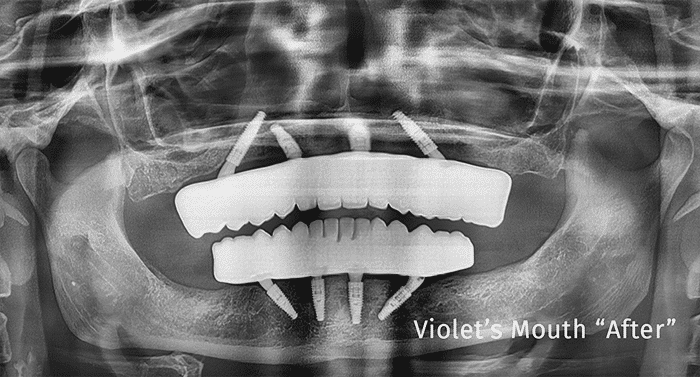

Patient teeth before full-mouth dental implant procedure Before

Patient smile after full-mouth dental implant transformation After